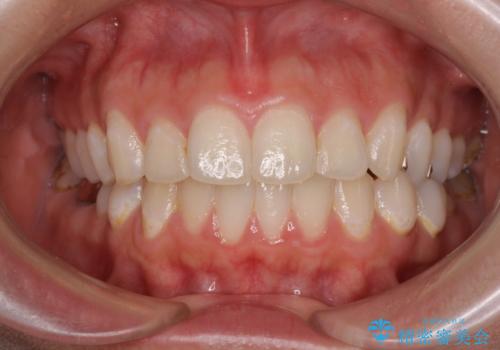

- 突き出た前歯を治したい 小臼歯抜歯+マルチブラケット矯正- 担当医 大元洋佑

- [抜歯] ワイヤー装置で出っ歯の改善![[抜歯] ワイヤー装置で出っ歯の改善の症例 治療前](https://seimitsushinbi.jp/wp/wp-content/uploads/2025/05/IMG_1672-500x350.jpg?v=1746632084) ![[抜歯] ワイヤー装置で出っ歯の改善の症例 治療後](https://seimitsushinbi.jp/wp/wp-content/uploads/2025/05/IMG_8070-500x350.jpg?v=1746632252)

- 【モニター】舌突出癖で隙間が ワイヤー装置での抜歯矯正

- 【モニター】口が閉じられない ワイヤー装置での抜歯矯正- 担当医 藤巻太一朗